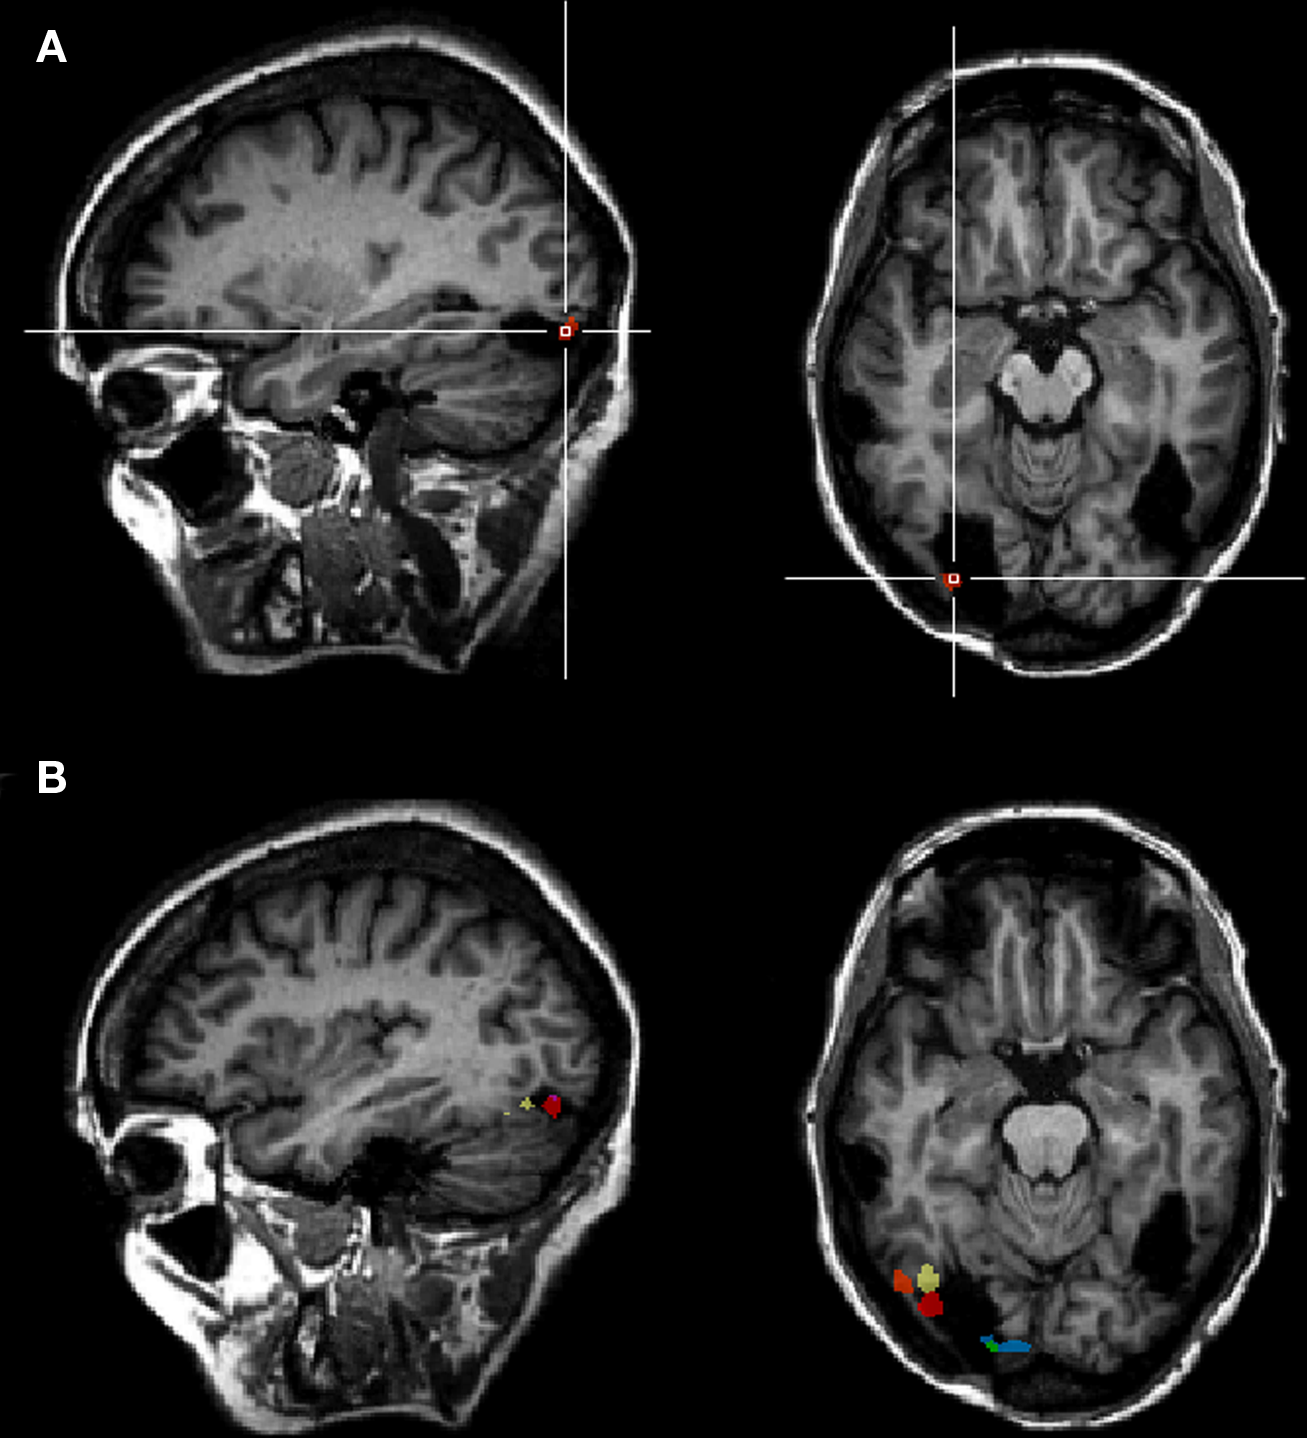

Whole-brain analysis

To strengthen our results, a whole-brain analysis was performed on PS’ data with the conjunction of the three contrasts (one per fMRI run: upright Mooney faces–inverted Mooney faces). Two clusters were found at p(uncorrected) < 0.05 in PS’ brain (Figure 7). The first one corresponds roughly to the FFA (31, −55, −17, 250 voxels). It shows a preferential response to faces over cars and scrambled faces in PS's face localizer (F–O: t = 8.34, p < 0.000001, F–SF: t = 8.36, p < 0.000001). The other one was located near the middle temporal sulcus (46, −49, −7, 122 voxels), and does not show a preferential response to faces in the localizer (larger for both objects and scrambled faces than faces: F–O: t = −1.45, p < 0.15 and F–SF: t = −2.11, p = 0.04). The same analysis was performed with AM (Figure 8), for which we also found two clusters: 34, −52, −13 (67 voxels; face-sensitivity: F–O: t = 15.25, p < 0.000001, F–SF: t = 26.31, p < 0.000001) corresponding exactly to her right FFA, and 52 −50 −5 (60 voxels) in the middle temporal sulcus (face-sensitivity: F–O: t = 10.27, p < 0.000001, F–SF: t = 11.35, p < 0.000001; note the proximity with the pSTS).

Figure 7

Whole-brain analysis performed on the patient PS in the Mooney face categorization experiment. Two areas were found to be significant, one corresponding roughly to the patient's right FFA, presenting face-preferential response to faces in the localizer experiment, and the other one in the middle temporal sulcus, which did not show a preferential response to faces in the localizer experiment.

Figure 8

Whole-brain analysis performed on the age-matched control (AM) in the Mooney face categorization experiment. As for the patient PS, two areas were found to be significant, one corresponding roughly to the right FFA, presenting face-preferential response to faces in the localizer experiment, and the other one in the middle temporal sulcus, which did not show a preferential response to faces in the localizer experiment.

With our seven participants considered as a group, we found only one significant cluster at p(uncorrected) < 0.05, corresponding to the Talairach coordinates of the right FFA (33, −42, −19, 344 voxels). This region showed a preferential response to faces as identified in the face localizer with the seven participants (F–O: t = 5.44, p < 0.000001, F–SF: t = 30.11, p < 0.000001). There was no significant activation in the right inferior occipital cortex, or the left hemisphere in this whole-brain analysis.

Importantly, we note that the whole-brain analysis of the face localizer in the same seven participants at the same statistical threshold [p(uncorrected) < 0.05] gave rise to a rFFA of 1124 voxels, and a rOFA of 359 voxels. The rOFA’ size was thus of 32% of the rFFA’ size in the face localizer experiment. Considering this proportion, one could have expected a rOFA of about 110 voxels in the Mooney experiment (32% of the 344 voxel size of FFA). Instead, there were no significant voxels in the right inferior occipital cortex above statistical threshold. The same reasoning can be made for the left FFA (494 voxels at p < 0.05; 151 voxels expected in the Mooney experiment, 0 found) and the left OFA (268 voxels at p < 0.05; 82 voxels expected, 0 found).

In summary, both the functional localizer approach and the whole-brain analysis indicate that the categorization of the stimulus as a face based on the Mooney stimuli takes place primarily in face-sensitive populations of neurons in the middle fusiform gyrus (FFA) of the right hemisphere, and to a lesser extent in the right posterior part of the STS. These areas are structurally intact in PS’ brain and they show the exact same response profile in fMRI in this task as for normal observers. Overall, these observations indicate that the categorization of the visual Mooney stimulus as a face does not rely on lower order visual areas that are sensitive to segmented face photographs in the localizer (OFAs), but is supported almost exclusively by higher order areas in the right hemisphere.